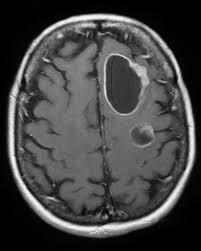

Signs Of Metastatic Breast Cancer In Brain / Metastatic Breast Cancer Warning Signs To Watch For - The most common types of cancer that cause metastatic brain tumors are cancers of the lung, breast, skin ( melanoma ), colon, kidney and thyroid gland.. Symptoms of brain metastases symptoms of brain metastases depend on the location, size and number of growths in the brain, or the amount of swelling. Jaundice or swelling in the belly, when cancer has spread to the liver. Though symptoms vary from patient to patient, common brain metastasis symptoms include: Pain and fractures, when cancer has spread to the bone. According to the national breast cancer foundation, the symptoms of metastatic breast cancer vary as far as type and severity depending on the site of metastasis (spreading).

Stroke or brain attack, in which blood supply to the brain is cut off; They are typically worse in the morning and lessen as the day goes on. Primary brain cancer occurs when a tumor develops in the brain while metastatic, however, refers to cancer that originated elsewhere in the body and then traveled to the brain. On the following pages you can read about: Though symptoms vary from patient to patient, common brain metastasis symptoms include:

Metastatic Breast Cancer Warning Signs To Watch For from images.ctfassets.net Nausea (feeling sick) or vomiting (being sick) can be caused by secondary breast cancer in the brain or elsewhere in the body, its treatment or emotional side effects such as anxiety. Headaches, sometimes with nausea and vomiting. Weakness of one side of the body, numbness, or tingling in the extremities: Stereotactic radiosurgery for brain metastasis. Some common signs of metastatic cancer include: Vomiting due to brain metastases tends to become worse and more frequent over time. Hemiparesis, weakness or paralysis of one side of the body, was the third most common neurological symptom of brain metastases in one study. The most common types of cancer that cause metastatic brain tumors are cancers of the lung, breast, skin ( melanoma ), colon, kidney and thyroid gland.

Signs and symptoms caused by brain metastases can vary based on the location, size and rate of growth of the metastatic tumors.

Metastatic breast cancer happens when the cancer spreads beyond the breast and lymph nodes, usually to the bones, liver, lungs, or brain. Headaches may be caused by a tumour pressing on the brain, swelling caused by a fluid buildup around the brain (called edema), bleeding or hydrocephalus. The symptoms of metastatic breast cancer can be very different depending on the location of the cancer: 9 warning signs of brain cancer. Primary brain cancer occurs when a tumor develops in the brain while metastatic, however, refers to cancer that originated elsewhere in the body and then traveled to the brain. In most cases, you also would continue with systemic treatments such as hormonal therapy, chemotherapy, and/or targeted therapies. Symptoms of brain metastases symptoms of brain metastases depend on the location, size and number of growths in the brain, or the amount of swelling. Bone, lung, brain, and liver. Symptoms can include sudden weakness or numbness on one side of the body, headache, trouble speaking, vision changes, dizziness and/or loss of balance Stroke or brain attack, in which blood supply to the brain is cut off; Vomiting due to brain metastases tends to become worse and more frequent over time. These are caused by a tumor creating pressure inside the skull, squeezing nearby brain tissue. Constant back, bone, or joint pain

These are the symptoms to watch for according to where mbc. Symptoms of breast cancer that has spread to the brain can include headache, changes in speech or vision, memory problems, and others. Other signs and symptoms of brain metastases include: Pain and fractures, when cancer has spread to the bone. Symptoms can include sudden weakness or numbness on one side of the body, headache, trouble speaking, vision changes, dizziness and/or loss of balance

Metastatic And Triple Negative Breast Cancer Challenges And Treatment Options Springerlink from media.springernature.com Signs and symptoms caused by brain metastases can vary based on the location, size and rate of growth of the metastatic tumors. it is common for people with metastatic breast cancer to develop metastases at multiple sites. An estimated 150,000 to 200,000 people are diagnosed with a brain metastasis each year, compared to about 17,000 diagnoses for primary. Not everyone with a brain metastasis will have symptoms but most do. Brain metastases are also much more common. Some common signs of metastatic cancer include: Bone, back, neck, or joint pain. It's important for your doctor to try to find out the cause so that it can be managed effectively.

In other cases, the body is able to. Persistent, progressively worsening headaches or pressure to the head There are two types of brain cancer known as primary and metastatic. The symptoms caused by a brain metastasis depend on the tumor's location. The women with brain metastasis, who had not yet developed symptoms at the time the metastases to the brain were discovered survived, on average, 10.4 months. Primary brain cancer occurs when a tumor develops in the brain while metastatic, however, refers to cancer that originated elsewhere in the body and then traveled to the brain. Metastases can push on or cause swelling in specific areas causing specific symptoms. Local therapies for brain metastasis include surgery and different types of radiation therapy. According to the national breast cancer foundation, the symptoms of metastatic breast cancer vary as far as type and severity depending on the site of metastasis (spreading). Symptoms can include sudden weakness or numbness on one side of the body, headache, trouble speaking, vision changes, dizziness and/or loss of balance These are the symptoms to watch for according to where mbc. Learn the signs and symptoms of metastasis, how you can make. The most common symptom of brain metastases is a headache.

The most common breast cancer metastasis sites are the bones, the lungs, the brain, and the liver. Headaches may be caused by a tumour pressing on the brain, swelling caused by a fluid buildup around the brain (called edema), bleeding or hydrocephalus. Brain surgeon and researcher rahul jandial of city of hope cancer center near los angeles explains common symptoms that could suggest brain metastasis in cancer survivors. Learn the signs and symptoms of metastasis, how you can make. They are distinct from primary brain tumors, which start in the brain.

Symptoms of brain metastases symptoms of brain metastases depend on the location, size and number of growths in the brain, or the amount of swelling. Other signs and symptoms of brain metastases include: Nausea (feeling sick) or vomiting (being sick) can be caused by secondary breast cancer in the brain or elsewhere in the body, its treatment or emotional side effects such as anxiety. Brain metastases are growths that spread to the brain from a cancer in another part of the body. Or, the cause of a symptom may be a different medical condition that is not cancer. However, for about 17% of women in this group, the brain is the only site of metastasis. The symptoms of metastatic breast cancer can be very different depending on the location of the cancer: They are distinct from primary brain tumors, which start in the brain. Signs and symptoms of brain metastases include: Headache, sometimes with vomiting or nausea mental changes, such as increasing memory problems An estimated 150,000 to 200,000 people are diagnosed with a brain metastasis each year, compared to about 17,000 diagnoses for primary. Persistent, progressively worsening headaches or pressure to the head Primary brain cancer occurs when a tumor develops in the brain while metastatic, however, refers to cancer that originated elsewhere in the body and then traveled to the brain.